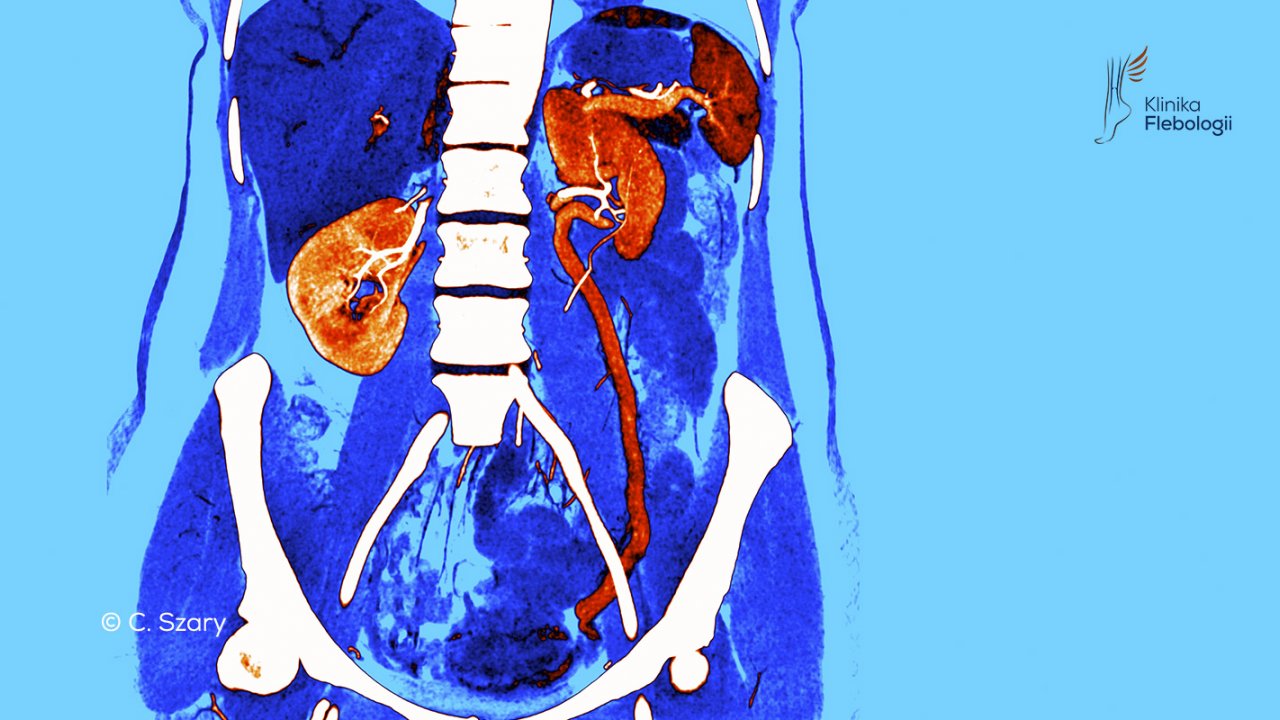

Anomalia spływu poszerzonej lewej żyły jajnikowej w wenografii TK